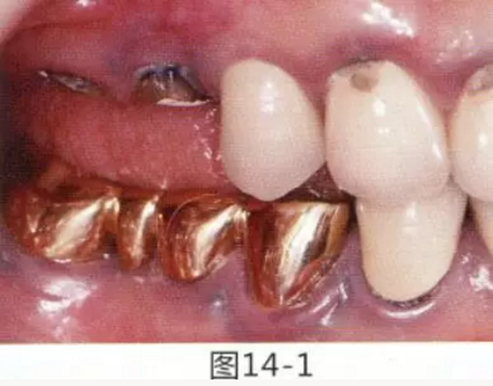

為了提高對修復體的術后效果,以生物學寬度,獲取附著齦為目的進行游離齦移植的病例。

圖14-1 修復體周圍角化牙齦較少,很難進行清潔的狀態(tài),并有緣下齲壞的發(fā)生。

圖14-2,3 徹底去除齲壞后,試圖通過游離齦移植獲取生物學寬度和附著齦。

圖14-7 配戴最終修復體完成5年后的狀態(tài)。保持良好。